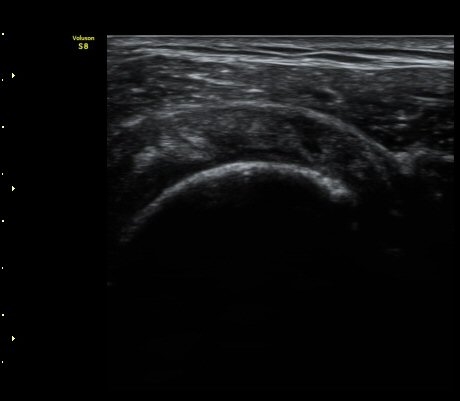

2049205267_d18eca99_IMG_20140331_2_1-c.jpg

2049205267_ba00cba1_IMG_20140331_2_3-c.jpg